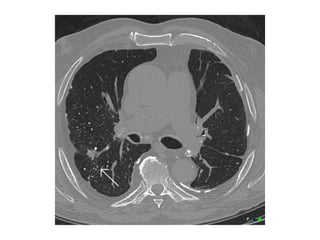

Centrilobular Emphysema

Panlobular Emphysema

Paraseptal Emphysema

Bullous Emphysema